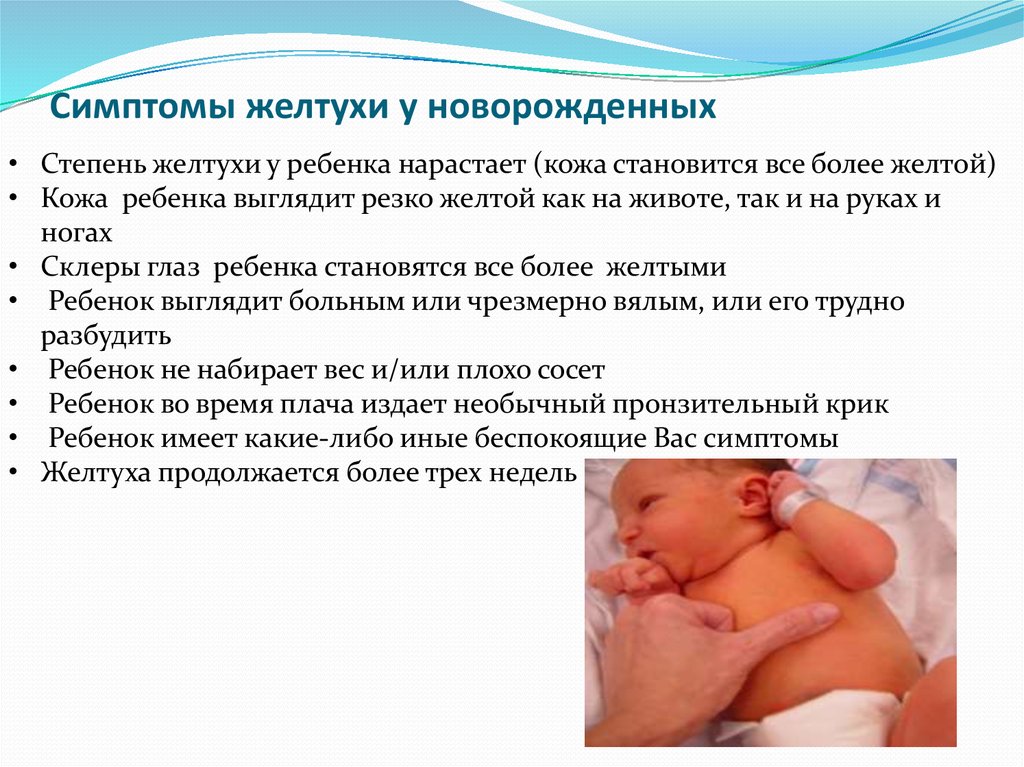

Срочного обращения за медицинской помощью требуют следующие симптомы:

- Желтуха появилась в первые 24 часа жизни

- Ректальная температура у ребенка 37,8°С и выше

- Интенсивная желтуха и/или распространяется по телу ребенка

- Ребенок выглядит больным, его трудно разбудить

- Ребенок возбужден, его трудно успокоить

- Тело или шея выгибаются

Желтуха считается физиологической и требует более широкого обследования, если: